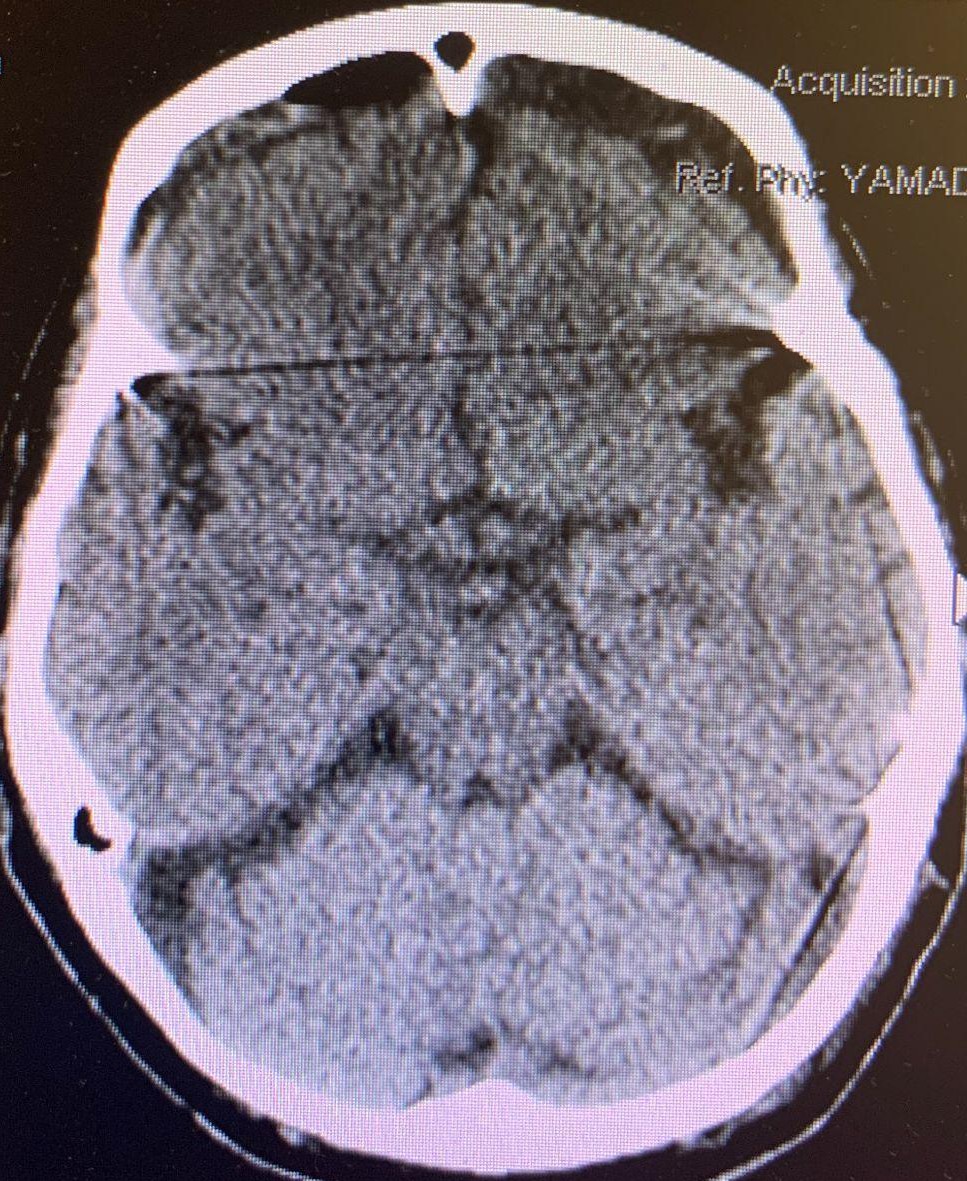

We reported a case of a 77-year-old right-handed female with a history of pre-diabetes, thyroid goiter, osteoporosis, hypertension, hyperlipidemia, transient ischemic attack/stroke on daily aspirin (ASA), presenting with one week of low-grade fever and generalized weakness. Patient had a fall in the bathroom and hit her head, prompting family members to bring the patient to the hospital. Computed tomography of the head (CTH) showed an old lacunar infarct in the right caudate nucleus, large acute on chronic subdural hematoma over the right frontoparietal region measuring up to 20 mm, and midline shift towards the left measuring 9.4 mm (Figure 1). On arrival, the patient was found to have significant sinus tachycardia, and the lab results were significant for urinary tract infection and chronic leukopenia. On exam, patient was awake, alert, oriented, with left facial droop, left drift, left sided weakness 4+/5.

Figure 1. CTH large acute on chronic subdural hematoma over the right frontoparietal region measuring up to 20 mm. Midline shift towards the left measuring 9.4 mm